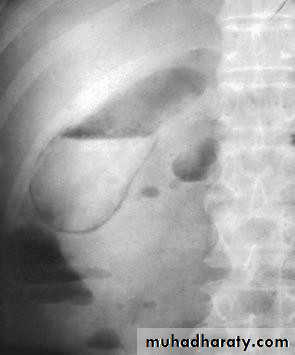

• Plain radiogaph:

• Radiopaque gall stones in 10%• Porcelain GB.. calcified GB..25% CA.

• Limey bile

• Gas in the wall, emphysematous cholecystitis

• Gas in the biliary tree;

• Porcelain GB

• Gas in gall bladder